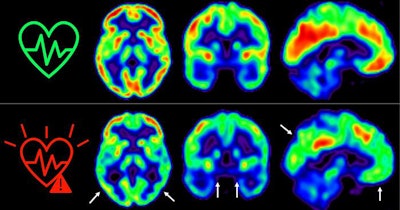

Researchers led by Catarina Tristao-Pereira studied F-18 FDG-PET scans of individuals with subclinical atherosclerosis. Over a five-year period, these high-risk individuals had a steeper decline in cerebral glucose metabolism compared with individuals at low risk.

According to the analysis, a persistent high risk of cardiovascular disease was associated with an accelerated decline of cortical F-18 FDG uptake compared with low-risk individuals. Specifically, on average, standard uptake value ratios (SUVRs) decreased by 61% per year in the whole cortex and by 77% per year in hypometabolic regions associated with Alzheimer's disease.

"Our results show that asymptomatic middle-aged individuals at high risk of cardiovascular disease over a five-year period have a steeper decline in cerebral glucose metabolism compared with individuals at low risk," the authors wrote.